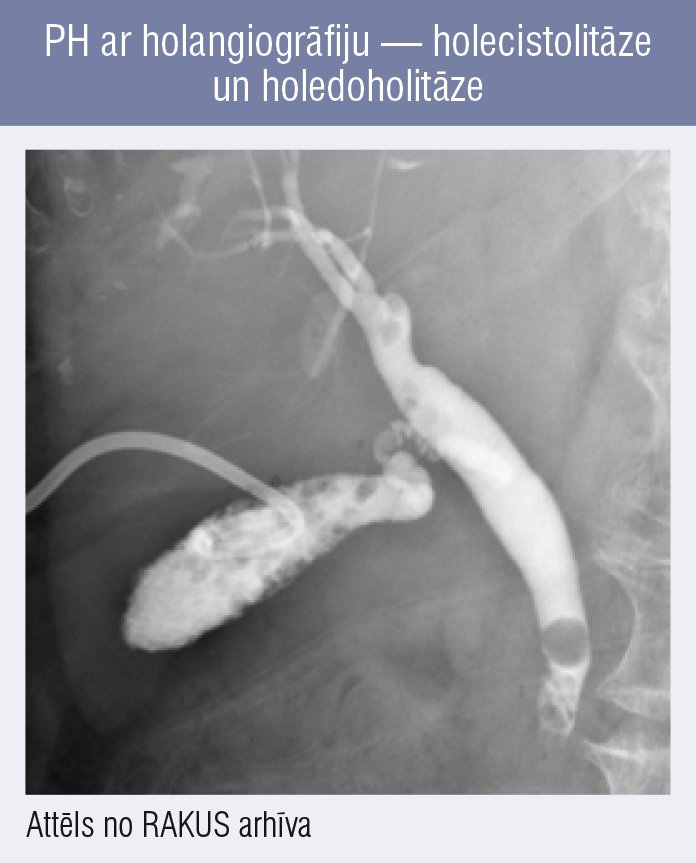

PH ar holangiogrāfiju — holecistolitāze un holedoholitāze PH ar holangiogrāfiju — holecistolitāze un holedoholitāze

5. attēls

PH ar holangiogrāfiju — holecistolitāze un holedoholitāze

PH var izmantot, lai pacientiem veiktu holangiogrāfiju un izmeklētu žultsceļu stāvokli, diagnosticētu, piemēram, holedoholitiāzi (4., 5. attēls) vai stenozējošu papillītu. PH ar žultsceļu kontrastēšanu jeb fistulogrāfija aprakstīta jau 1979. gadā, [18] tā ir pietiekami jūtīga metode [19; 20] un var būt kā alternatīva magnētiskās rezonanses holangiopankreatogrāfijai (MRHP).

Vienā no jaunākajiem 2022. gadā publicētajiem rakstiem minēts, ka PH ar sekojošu holangiogrāfiju rekomendējama katram pacientam ar AH, jo tas var mainīt ārstēšanas taktiku pat 30 % pacientu. [19]

Arī mūsu klīnikā PH ar holangiogrāfiju veic nedaudz vairāk nekā pusei no pacientiem ar PH, bet tā nav rutīnas metode.